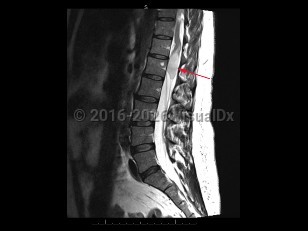

Tuberculous spondylitis